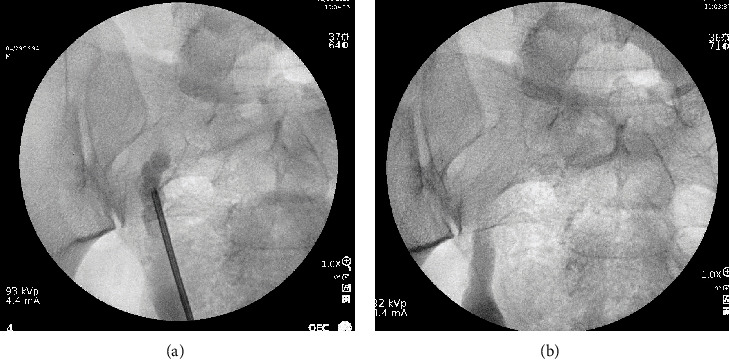

Zinner syndrome is a rare congenital anomaly characterized by a triad of renal dysgenesis/agenesis, cysts in the ipsilateral seminal vesicle, and ejaculatory duct obstruction. Though often diagnosed in infancy, the diagnoses can be incidentally found in adults who present with nonspecific genitourinary symptoms including dysuria, ejaculatory dysfunction, or genital pain. We present an unusual case of a 29-year-old male patient who presented to the emergency department with recurrent testicular pain and hematospermia and was found to have an atrophic right kidney with an ectopic ureter implanting into a cystic seminal vesicle. These findings were consistent with a rare subvariant of Zinner syndrome only previously described four times in the literature. We performed a robotic-assisted laparoscopic ectopic nephroureterectomy with sparing of his seminal vesicle. To our knowledge, this is the first report to describe the safe and effective use of robotic surgery in this setting to remove affected anatomy while preserving the patient's seminal vesicle.